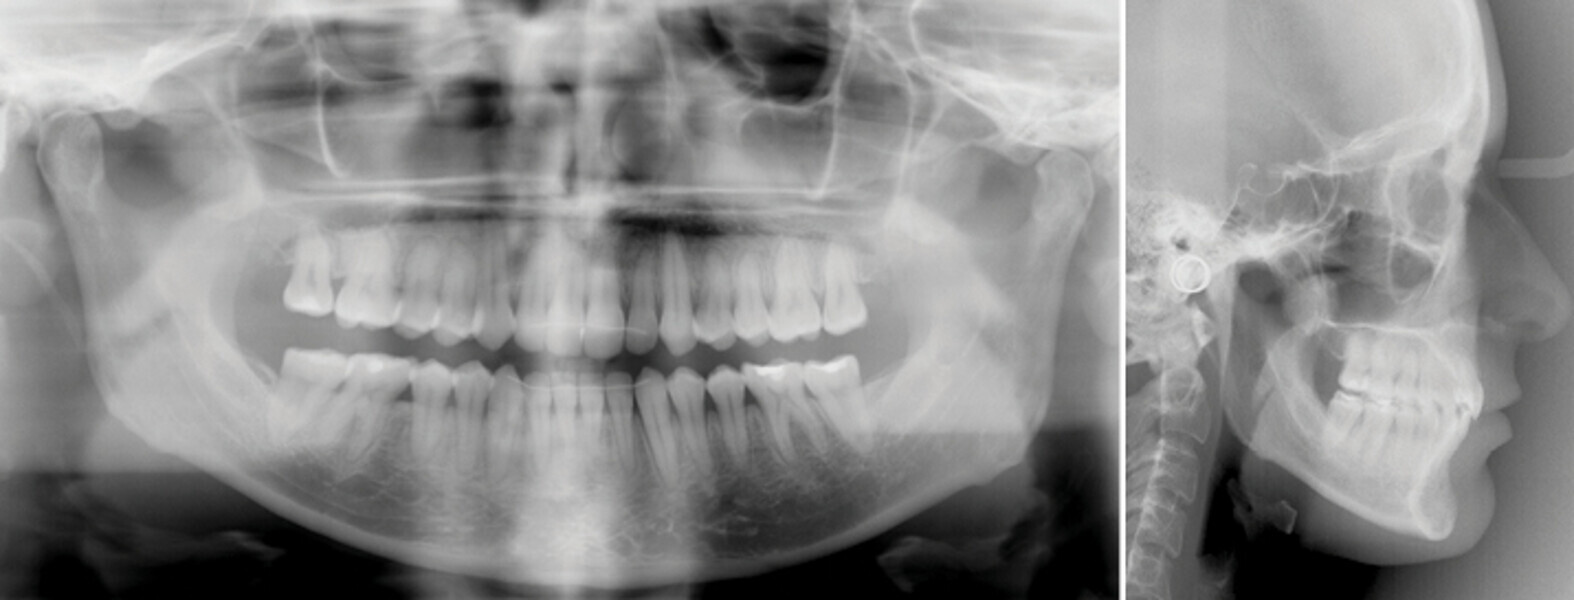

Řešení otevřeného skusu u dospělého pomocí Insignia™ systému a Straight-Wire™ finishingu